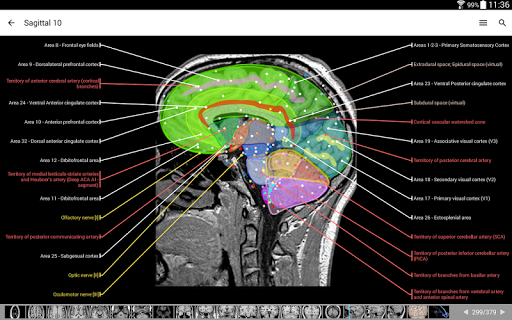

- وحدتان جديدتان: الدماغ - TOF والأوعية الدموية الدماغية ، أطلس التشريح الوعائي العصبي الطبيعي لشرايين الدماغ على الأوعية الدموية الدماغية. - تم إعادة صياغة الواجهة. - تتوفر علامة تبويب جديدة باسم "QuickLinks" ، ترسل وحدات في أقسام من جسم الإنسان وتسمح لك بالسفر السريع إلى الوحدات التي تبحث عنها. الخلل الصغيرة الثابتة.